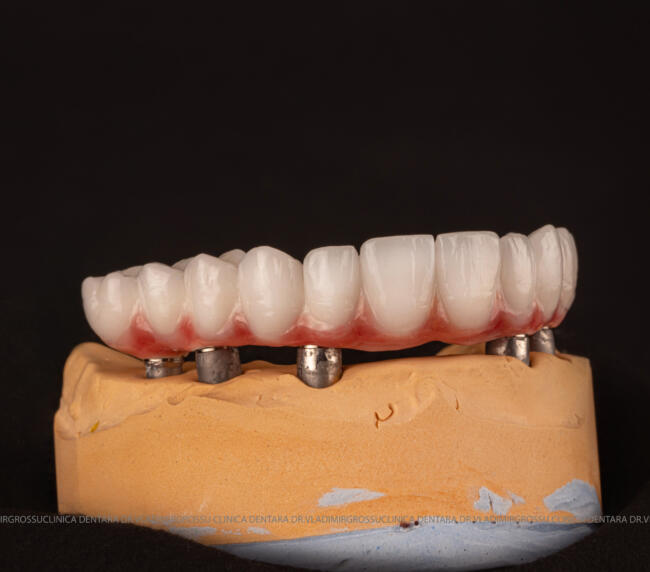

Pentru protezarea definitivă:

- Șase abutment-uri permanente pe multiunit-uri;

- Proteză definitivă realizată din metaloceramică sau zirconiu, cu 12-14 unități (soluția recomandată).

- Posibilitatea realizării unei proteze cu 12-14 dinți, oferind un aspect estetic natural și funcționalitate optimă.